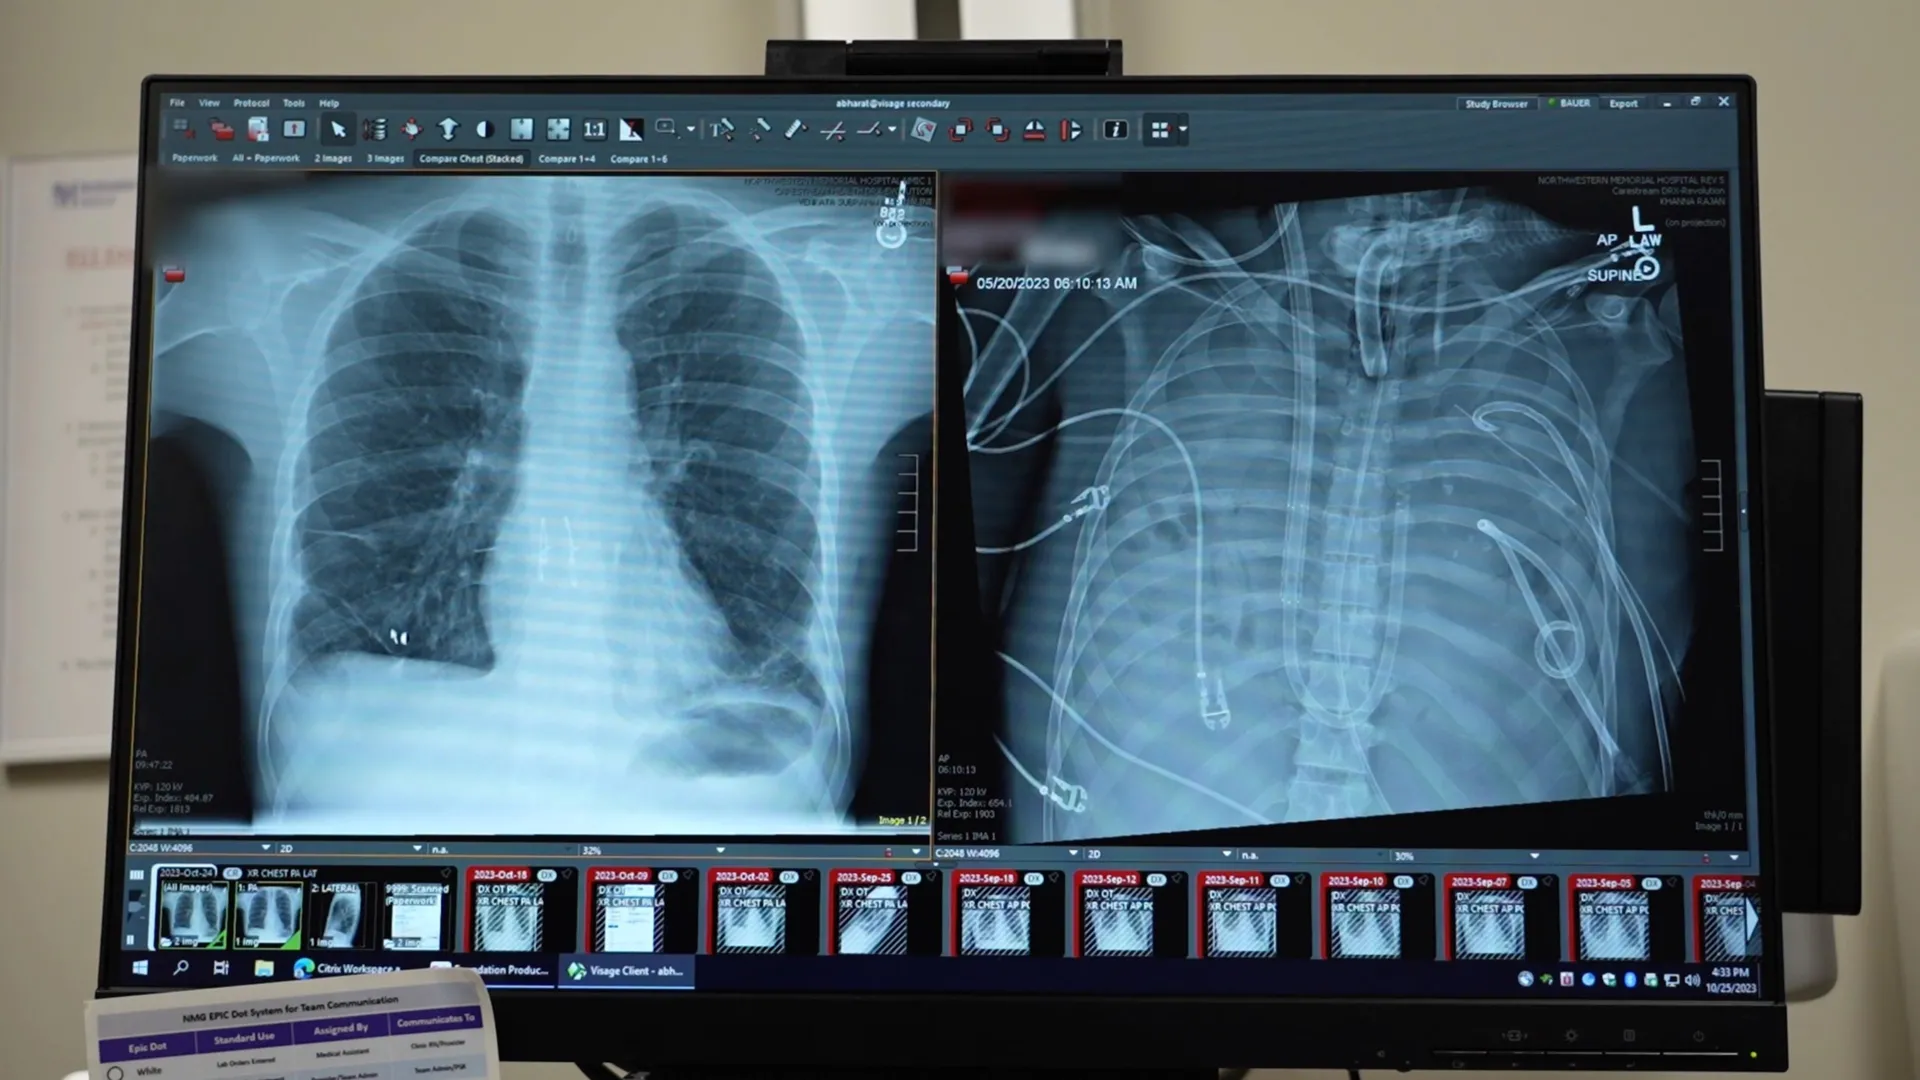

This question propelled the development of an innovative extracorporeal membrane oxygenation (ECMO) system, specifically adapted to function as an "artificial lung." This sophisticated apparatus was designed to temporarily assume the critical functions of the patient’s native lungs. It meticulously oxygenated his blood, efficiently removed carbon dioxide, and crucially, provided circulatory support. This allowed his heart and other vital organs to continue functioning, creating a vital window of opportunity for recovery and transplant.

Following the radical decision to remove the diseased lungs, the patient’s condition began to show signs of stabilization. The artificial lung system effectively managed his oxygenation and carbon dioxide levels, alleviating the immense pressure on his cardiovascular system. As a result, his blood pressure normalized, his failing organs began to show signs of recovery, and the rampant infection started to recede.

The critical 48-hour period was a testament to the efficacy of the artificial lung system. During this time, the medical team meticulously monitored the patient’s vital signs, managed his infection, and prepared for the eventual transplant. The availability of donor lungs, often a significant hurdle in transplant medicine, arrived at the opportune moment.

Two days after the removal of his native lungs and the implementation of the artificial lung, donor lungs became available. The surgical team, now working with a more stable patient, successfully executed a complex double lung transplant. The long-term prognosis for the patient has been overwhelmingly positive. More than two years following the procedure, he is reportedly living a normal life, with healthy and fully functional transplanted lungs.